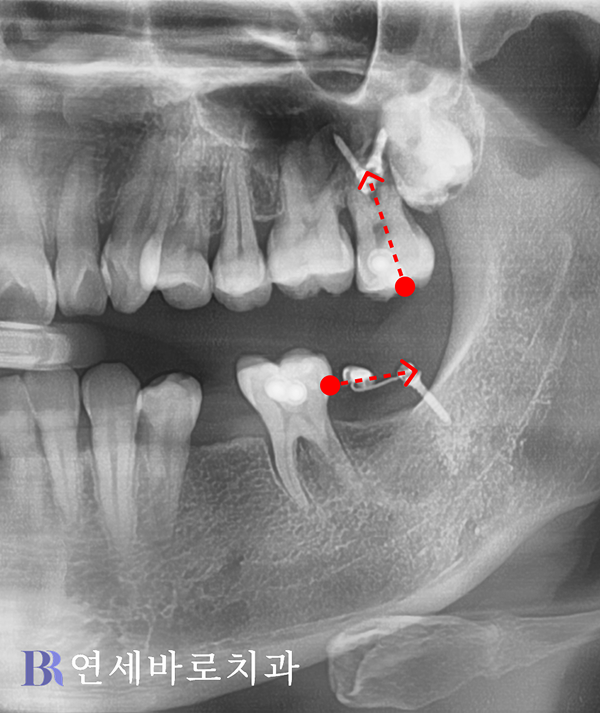

여기에 본인도 동의하셨고,

수술 전에 교정을 먼저

진행하기로 결정하였습니다.

하악에서는 쓰러진 어금니를

올바른 각도로 세웠으며,

아래로 내려온 상악 치아에는

상방 견인을 도모했습니다.

나중에 윗니가 내려오지 않게

사랑니도 발치하였습니다.

이렇게 부분교정이 마무리되고

매식체를 식립하기 위해서

본격적인 수술이 이어졌습니다.